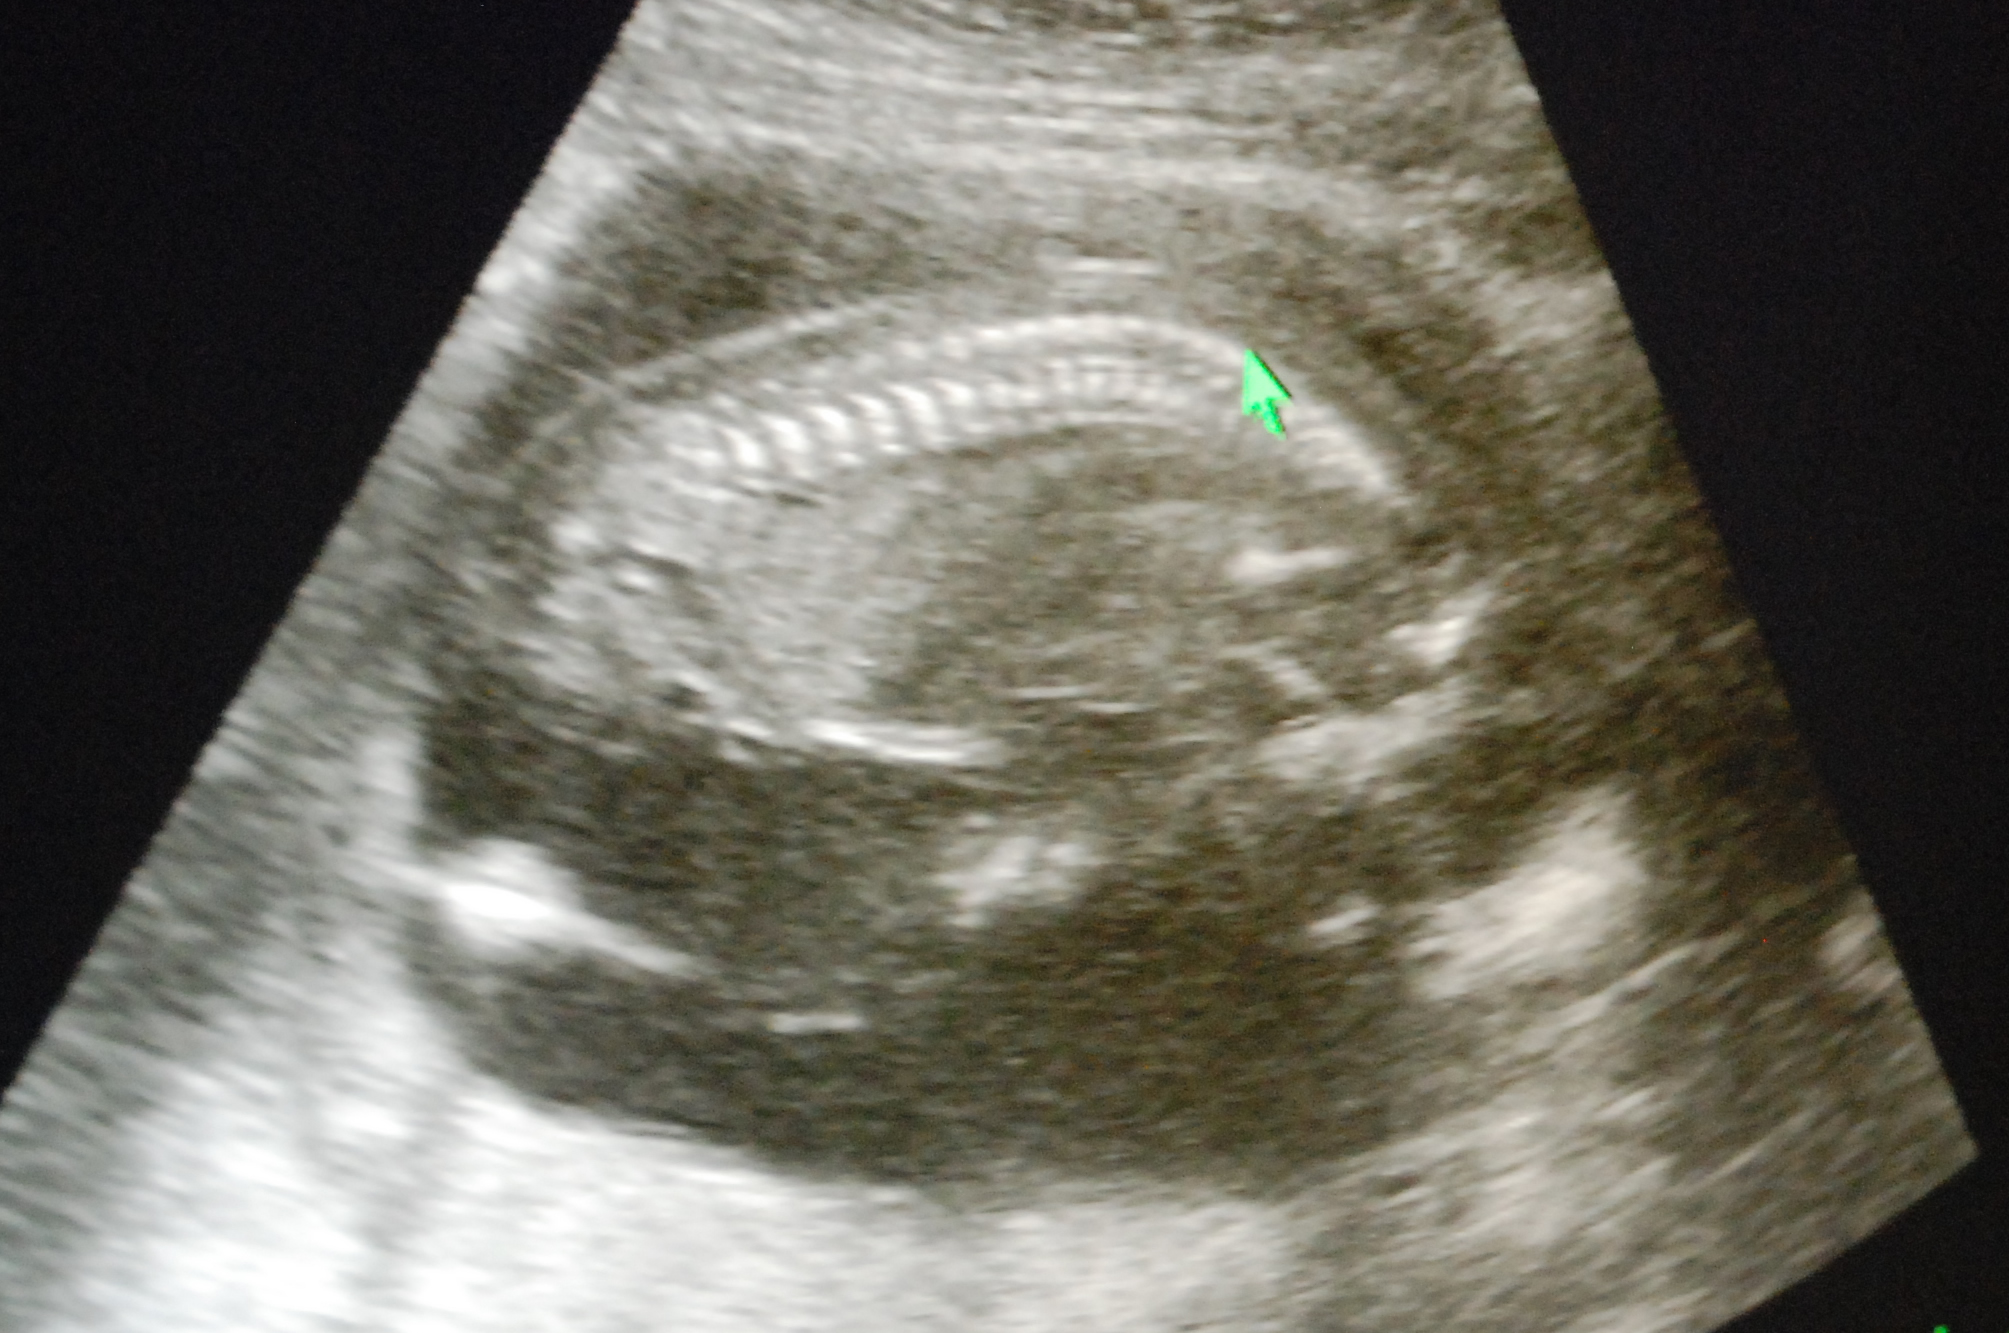

怀孕

育儿

在瑞典生宝宝 - 1怀孕篇